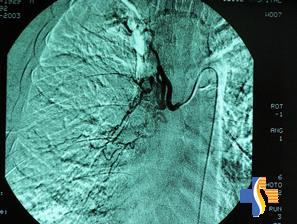

5.血管造影(1)選擇性支氣管動脈造影:近年的1組資料顯示,306例咯血病人中,出血來自支氣管動脈者280例(占91.5%),來自肺動脈者26例(僅占8.5%)。另1組對72例大咯血病人的研究發現,出血來自肺動脈者也僅占8.4%。可見咯血病人的出血,絕大部分來自支氣管動脈系統。選擇性支氣管動脈造影不僅可以明確出血的準確部位,同時還能夠發現支氣管動脈的異常擴張、扭曲變形、動脈瘤形成以及體循環-肺循環交通支的存在,從而為支氣管動脈栓塞治療提供依據。

(3)選擇性支氣管動脈栓塞術:根據肺部受支氣管動脈和肺動脈的雙重血供,兩套循環系統間常存在潛在交通管道,並具有時相調節或相互補償的功能。當支氣管動脈栓塞後,一般不會引起支氣管與肺組織的壞死,這就為支氣管動脈栓塞術治療大咯血提供了客觀依據。近20年來,動脈栓塞術已被廣泛套用於大咯血病人的治療。尤其是對於雙側病變或多部位出血;心、肺功能較差不能耐受手術或晚期肺癌侵及縱隔和大血管者,動脈栓塞治療是一種較好的替代手術治療的方法。栓塞治療通常在選擇性支氣管動脈造影,確定了出血部位的同時進行。但當患者X線胸片陰性、雙側均有病變或一側病變不能解釋出血來源時,選擇性支氣管動脈造影將無法進行。這時先行纖維支氣管鏡檢查,常能幫助明確大咯血的原因及出血部位,從而為選擇性支氣管動脈造影和支氣管動脈栓塞術創造條件。一旦出血部位明確以後,即可採用吸收性明膠海綿(明膠海綿)、氧化纖維素、聚氨基甲酸乙酯或無水酒精等栓塞材料,將可疑病變的動脈儘可能全部栓塞。如果在支氣管及附屬系統動脈栓塞以後,出血仍持續存在,需考慮到肺動脈出血的可能。最多見的是侵蝕性假性動脈瘤、肺膿腫、肺動脈畸形和肺動脈破裂。此時還應對肺動脈進行血管造影檢查,一旦明確病變存在,主張同時做相應的肺動脈栓塞。支氣管動脈栓塞術治療大咯血的近期效果肯定,一般文獻報導有效率可達80%左右。但這畢竟只是一種姑息療法,不能代替手術、消炎、抗癆等病因治療。注意當造影顯示,脊髓動脈是從出血的支氣管動脈發出時,栓塞是禁忌的,因為這有造成脊髓損傷和截癱的危險。